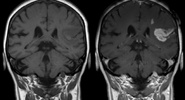

Положение опухоли оказывает воздействие на уровень пролактина, вызывая нарушения менструального цикла и бесплодие.Царьград